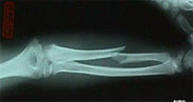

Las fracturas del cúbito y radio son las más frecuentes de la infancia y tienen lugar generalmente por caídas en lugares de recreo y durante la práctica deportiva. En la edad adulta los accidentes de tráfico y los deportes de contacto son las causas más frecuentes de lesión a este nivel. El tratamiento depende del tipo de fractura y grado de desplazamiento. Se realizará tratamiento conservador siempre que la fractura lo permita relegando el tratamiento quirúrgico a aquellas fracturas difícilmente estabilizables mediante escayola.

La articulación de la muñeca une las regiones del antebrazo y la mano implicando la porción inferior del cúbito y radio así como los huesos del carpo.Las fracturas del radio distal son las más frecuentes de la extremidad superior. En gente joven se asocian a traumatismos de alta energía como accidentes de tráfico, caídas desde altura o accidentes deportivos. En el anciano lacarencia de hueso a este nivel (osteoporosis) hace de esta región un lugar muy susceptible de fractura con pequeños impactos.

El paciente de edad se beneficia habitualmente del tratamiento conservador con escayola. En el paciente joven el desplazamiento suele ser difícilmente manejable con inmovilización con yeso por lo que es frecuente la realización de una pequeñaintervención para la recuperación anatómica de la muñeca pudiendo reincorporarse a su actividad habitual en el menor tiempo posible y con el menor riesgo de complicaciones.Dentro de la región anatómica de la muñeca se encuentran los huesos del carpo. El hueso escafoides es el que se fractura con más frecuencia tras caídas sobrela mano en extensión. Es por ello una lesión característica en deportes como motociclismo, ciclismo y patín donde se pueden sufrir traumatismos a gran velocidad. El dolor se localiza siguiendo el eje del pulgar pero a nivel de la muñeca y el dolor a la palpación en esta zona (tabaquera anatómica) es extremo. Las fracturas desplazadas se suelen estabilizar quirúrgicamente sin cicatriz,a través de la introducción percutánea de un tornillo intraóseo que permite el inicio de la movilización de la articulación inmediatamente.